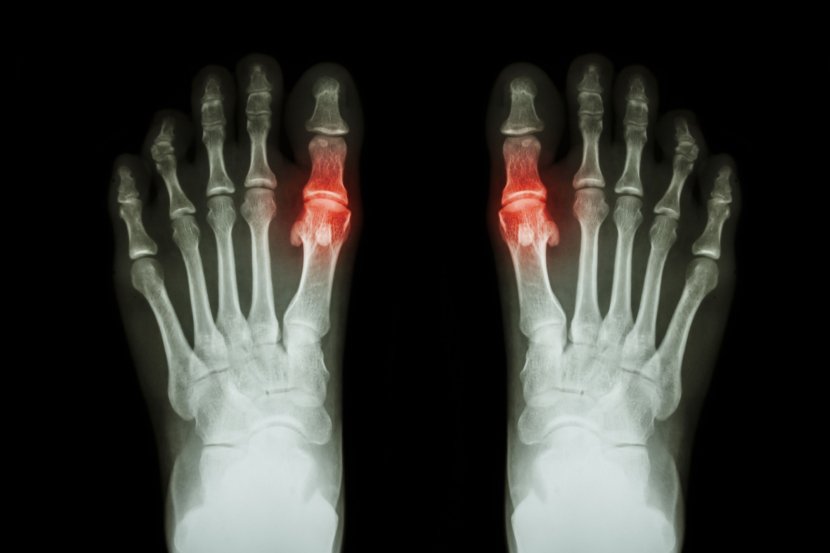

Metatarzofalangealni zglob povezuje kosti prstiju sa kostima stopala. Metatarzalne kosti su duge kosti koje povezuju srednje i zadnje stopalo sa prstima, a između glava metatarzalnih kostiju i dna proksimalnih falanga (kosti prstiju) nalaze se metatarzofalangealni zglobovi. Ovi zglobovi, poznati i kao MTP zglobovi, okruženi su tankom zglobnom kapsulom i imaju ligamente koji ih podržavaju. Poznati su i kao zglobovi velikog prsta.

Giht - Giht je oblik artritisa koji može da utiče na stopalo, posebno na prvi metatarzofalangealni zglob. Kada u telu ima previše mokraćne kiseline, to može dovesti do stvaranja bolnih kristala u zglobovima. Simptomi napada gihta su iznenadni, jak bol, crvenilo, otok i toplotu nožnog prsta.